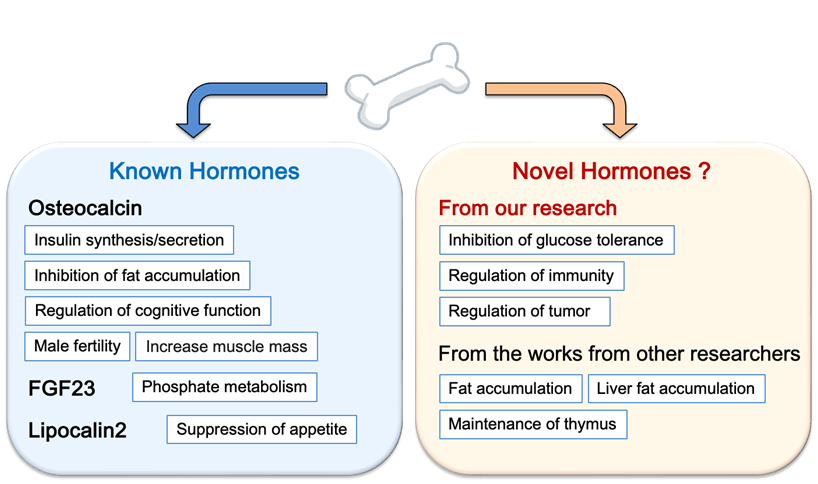

B. Elucidation of homeostatic mechanisms to control other organs by the musculoskeletal system

Recently I have discovered a novel endocrine action of bone that cannot be explained by known bone hormones (unpublished). Therefore, I am now analyzing to discover novel bone hormones and to elucidate new mechanisms of regulation of biological functions by bone tissue. Currently, we are screening candidates for novel bone hormones and analyzing them at the molecular, cellular, and individual levels.